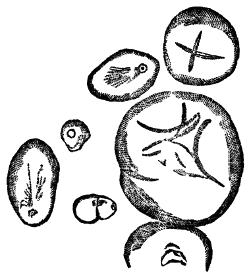

IPECACUAN′HA. Syn. (Ipecacuanha, L.; Ipecacuhan, E., B. P.) Radix ipecacuanhæ, Ipecacuanha (Ph. L. E. & D.), L. The dried root of Cephaëlis Ipecacuanha, or the true ipecacuanha plant, one of the Cinchonaceæ. “Ashy coloured, tortuous, very much cracked, and marked in rings with deep fissures, having an acrid, aromatic, bitterish taste.” (Ph. L.) It occurs in pieces 3 or 4 inches long, and about the size of a writing quill.—Dose. As an emetic, 10 to 20 gr., assisted by the copious use of warm water; as a nauseant, 1 to 3 gr.; as an expectorant and sudorific, 1⁄2 to 1 gr. It is undoubtedly the safest and most useful medicine of its class. It has recently been highly recommended in dyspepsia, combined with other bitters or aperients. Almond meal is sometimes used as an adulterant in ipecacuanha powder.